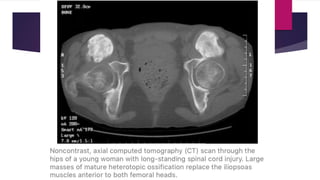

 Patients with complete injury to cord are more likely to develop HO.

 Always develop below level of injury.

 Hips are the most common site.

 The disease is often more extensive involving various sites together.